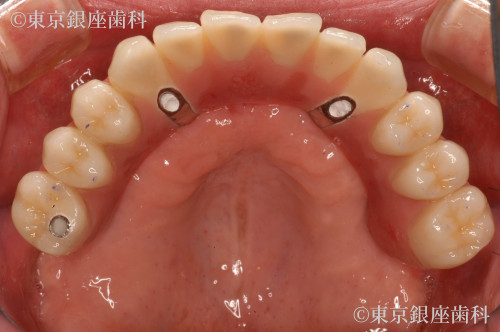

昔行ったインプラントからワンデイインプラントに変更

歯周病が進行したため、上下でワンデイインプラントを実施